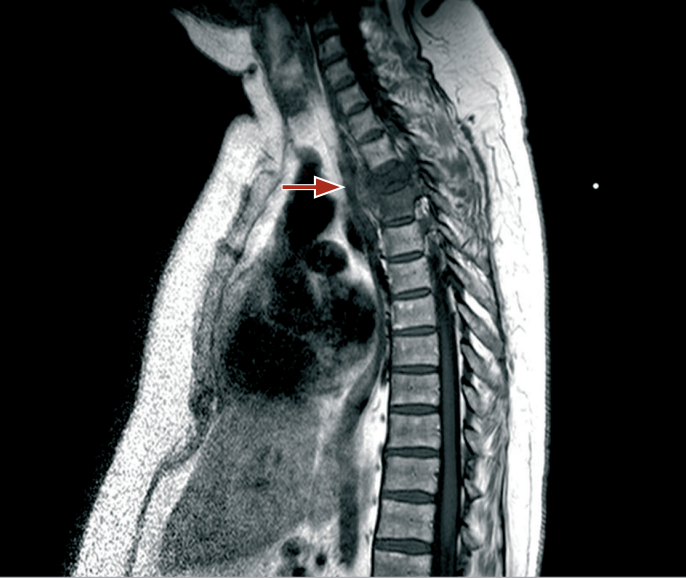

Die MRT der Wirbelsäule mit Kontrastmittel zeigte eine Zerstörung der Bandscheibe D3–D4, osteolytische Läsionen der Wirbelkörper sowie eine hohe Signalintensität in den STIR-Sequenzen, was auf einen entzündlichen Prozess mit begleitender epiduraler und pleuraler Abszessbildung hindeutet. Eine CT-gesteuerte Biopsie wurde sowohl zur therapeutischen Drainage der eitrigen Ansammlung als auch zu diagnostischen Zwecken durchgeführt, wobei paravertebrales und pleurales Material entnommen wurde. Die Kulturen des Exsudats fielen positiv auf Staphylococcus aureus aus. Eine empirische Antibiotikatherapie wurde mit Teicoplanin 600 mg/Tag begonnen, gefolgt von Rifampicin 600 mg/Tag und Levofloxacin 500 mg/Tag.

MRT der Wirbelsäule mit Kontrastmittel: bei T1 ist eine Hypodensität des Wirbelkörpers zu erkennen